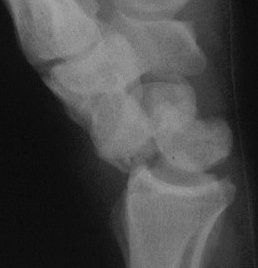

Case 5. Another,same bidirectional technique. Here, I ran the second screw too close to the first, and may have flattened the leading threads - not

ideal. The preop status:

With intercalated iliac bone graft...

Click for larger image